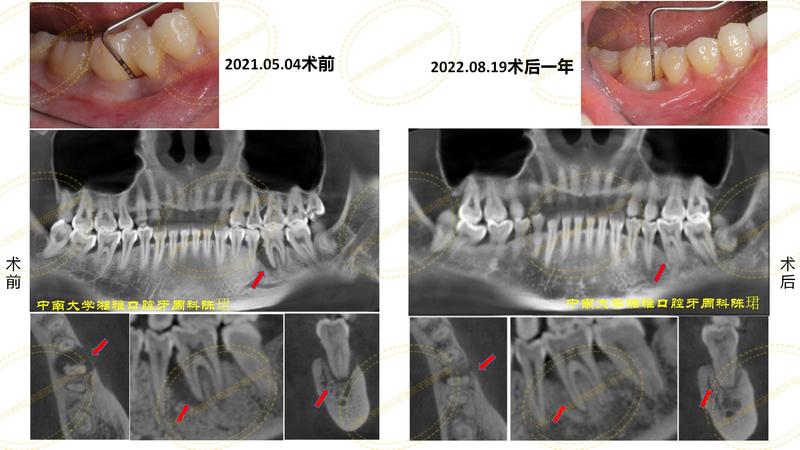

患者是一名來自江西的32歲女性,一年前因為36牙II度松動,當?shù)蒯t(yī)院建議她拔了,但是她不想年紀輕輕就拔了,所以就來到我們科就診,經(jīng)過規(guī)范的牙周基礎治療和GTR聯(lián)合植骨術后36牙得以保留,目前36不松動、36近中牙周袋從術前的10mm降到目前只有4mm,cbct顯示36牙槽骨再生良好。